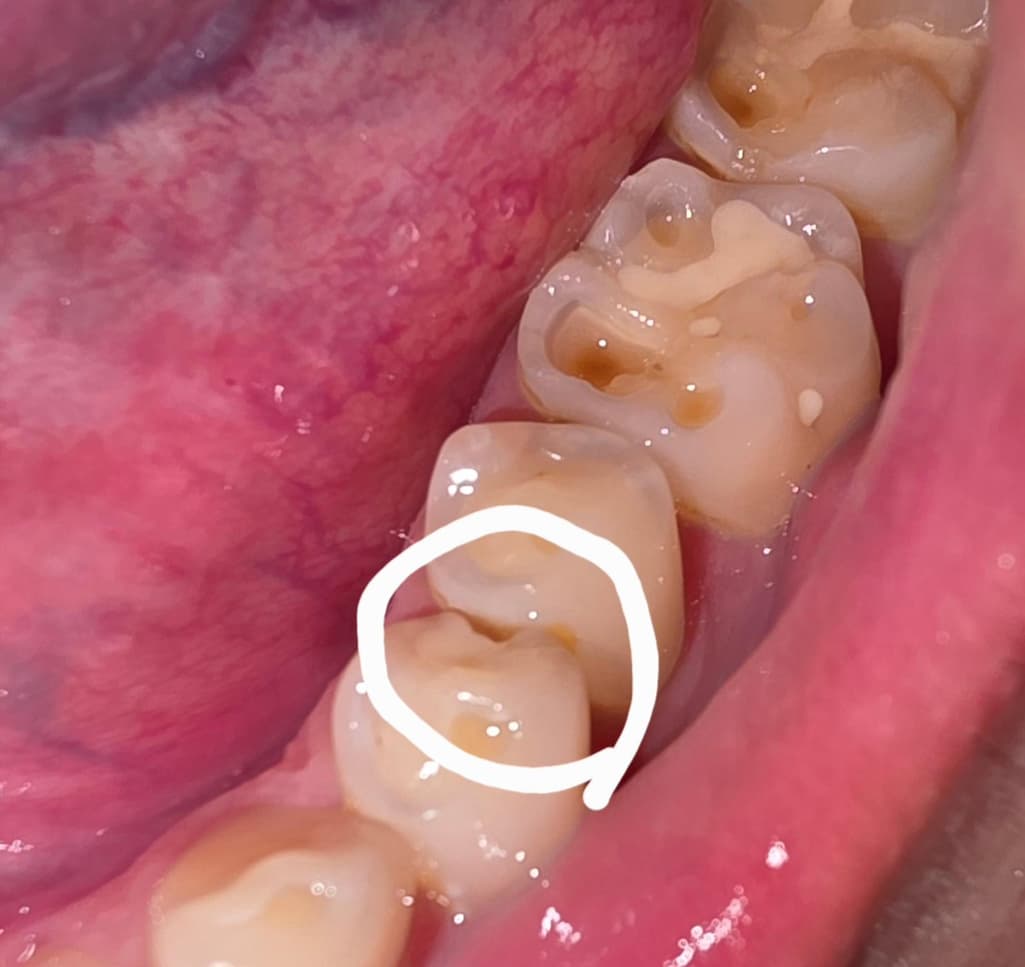

이가 깨진거같은데 치료가 복잡할까요??

이가 어느샌가 보니 홈이 생겨져 잇드라구요

동그라미 친부분 여긴 어떻게 치료하나요??....그냥 레진으로도 메꿀수잇나요??

시린느낌이나 통증은없어요...

치아 사이가 깨진거 같습니다. 충치가 심하지 않으면 인레이 치료를 하시면될것같습니다.

사진만으로는 알 수 없으며 해당 부위에 충치가 있을 가능성이 높아 간단하게 떼우긴 힘들 수 있습니다.

저 치아 뿐만 아니라 깨져나간 치아가 여러개 있네요 치료는 레진으로 떼우면 되는데 저렇게 다수 치아가 깨져나가는 원인(이갈이, 이악물기 등..) 을 찾아 개선해주면 더 좋을 것 같습니다

레진은 10~15만원 합니다

사진으로 봤을 경우 인접면에 충치로 인해서 파절이 된것으로 보입니다. 인접면에 충치가 있거나 충전제가 깨진것이라면 보철치료가 필요할수 있습니다.

자세한 확인을 위해서 치과에서 진료를 받아보는 것을 권유드립니다.